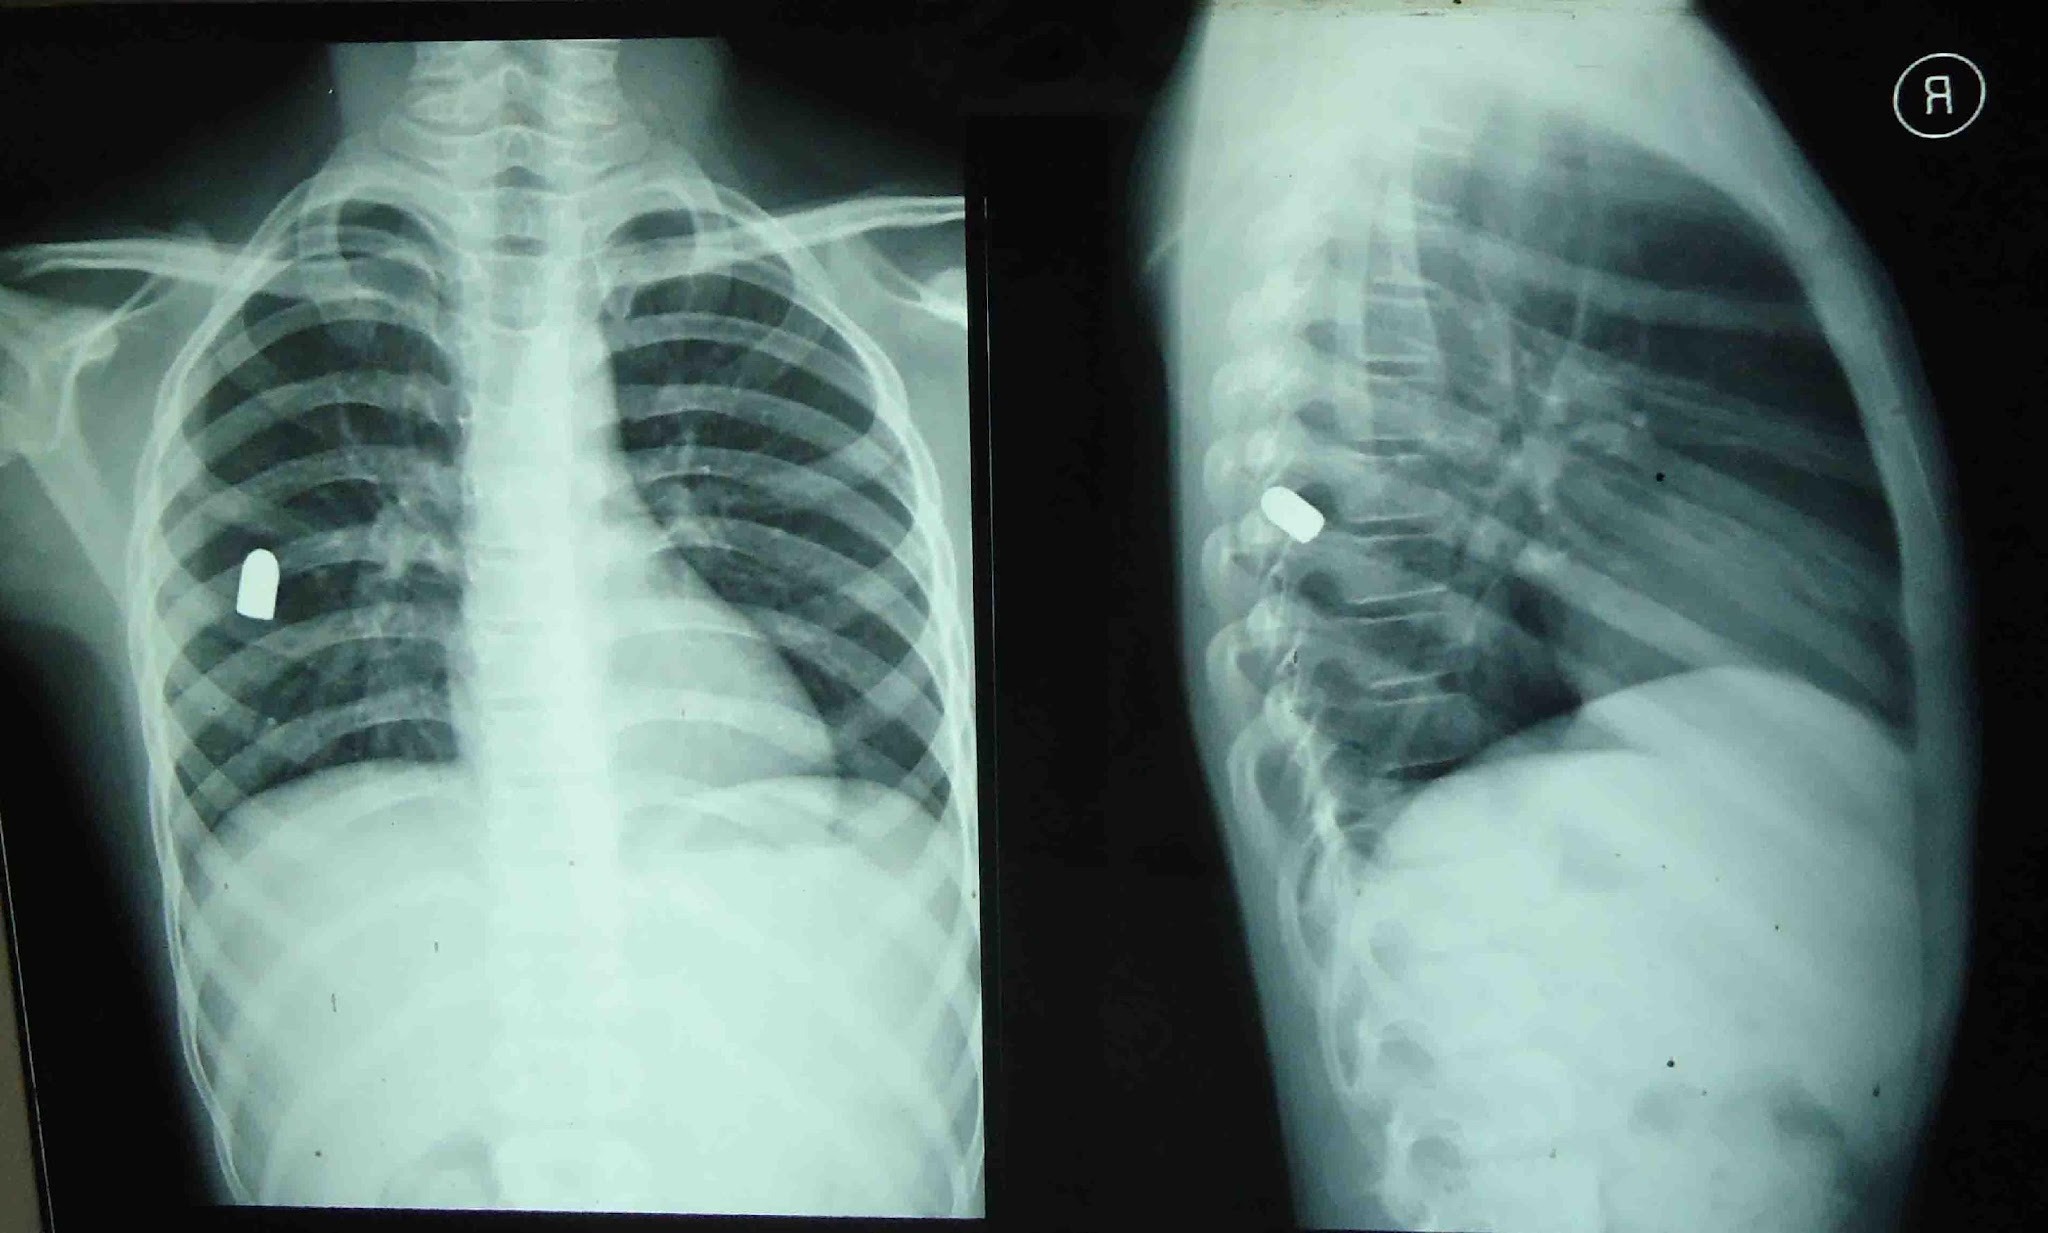

Metal Density

The highest density appearing as bright white on imaging, indicating the presence of metal objects.